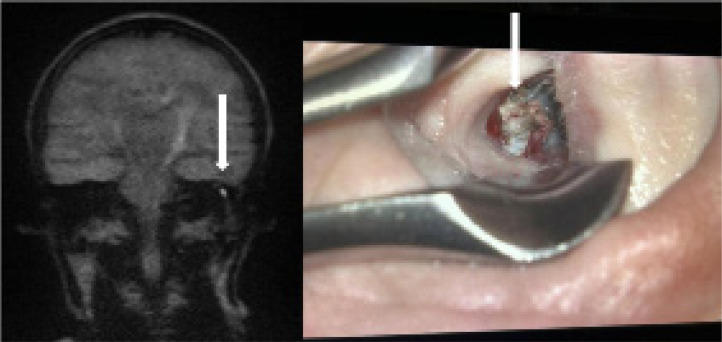

Results: Clinical and radiological concordance was found in 80% of patients. True positive results were observed in 77.5% of cases, while true negative results were noted in 2.5%. False positive results occurred in 8% of cases, mainly due to wax in the external auditory canal. False negative results were found in 12% of cases, often due to small or mural cholesteatomas. The sensitivity of MRI DWI non-EPI in detecting cholesteatoma was 87%.

Conclusions: MRI DWI non-EPI is an effective tool for detecting cholesteatoma recurrence, potentially avoiding unnecessary second-look surgeries. Awareness of false positive and negative results is crucial, and correlation of MRI findings with clinical examinations is recommended. To minimise false results, ear cleaning before MRI and repeated examinations at intervals are advised.